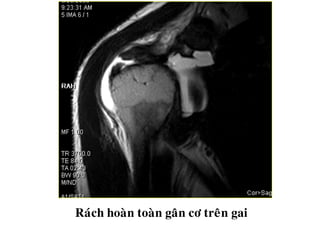

Raùch hoaøn toaøn gaân cô treân gai

Rách chóp xoayhoàn toàn • - Khuyết gân lan đến cả hai mặt. • - Tín hiệu dịch trong vùng khuyết trên T2W

Vị trí rách -Gân cơ trên gai là vị trí thường gặp nhất - Rách lớn lan đến gân cơ dưới gai. Rách đơn độc gân cơ dưới gai hiếm. - Gân cơ dưới vai bị tổn thương trong trường hợp rách nhiều hoặc chấn thương nặng - Hiếm khi tổn thương cơ tròn bé - Tìm tổn thương gân cơ nhị đầu, đặc biệt khi rách lớn

Raùch hoaøn toaøngaân cô treân gai